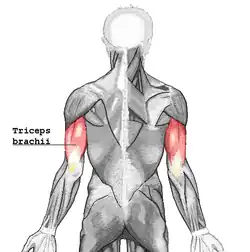

Tríceps braquial

| Tríceps braquial. Vista posterior. | |

O músculo tríceps braquial ou tricípete braquial é um largo músculo esquelético de três cabeças encontrado em humanos. Ele corre na superfície posterior do braço.

O músculo tricípete braquial é geralmente chamado de "tríceps". Entretanto, o termo "tricípete" (em Latim significa "três cabeças") pode ser usado para qualquer músculo que possua três origens.